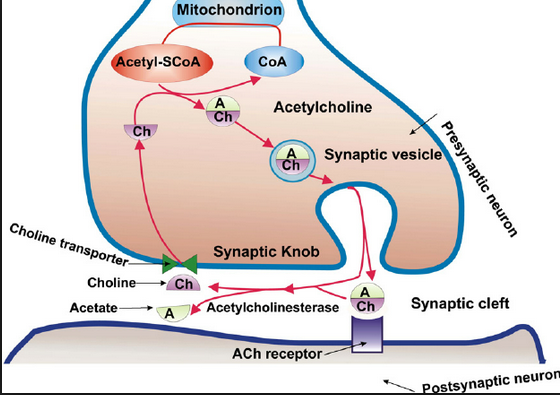

and the LINK to the bio-molecular communications molecule ……ace –> acetylcholine

Acetylcholine – Wikipedia, the free encyclopedia

https://en.wikipedia.org/wiki/Acetylcholine

Wikipedia

Acetylcholine is an organic chemical that functions in the brain and body of many types of animals, including humans, as a neurotransmitter—a chemical …

History · Function · Synthesis and degradation · Receptors

Acetylcholine Neurotransmission (Section 1, Chapter 11 …

neuroscience.uth.tmc.edu › Table of Contents

11.1 Introduction. Acetylcholine, the first neurotransmitter discovered, was originally described as “vagus stuff” by Otto Loewi because of its ability to mimic the …

Acetylcholine – Neuroscience – NCBI Bookshelf

www.ncbi.nlm.nih.gov › … › Bookshelf

National Center for Biotechnology Information

by D Purves – 2001

Acetylcholine is the neurotransmitter at neuromuscular junctions, at synapses in the ganglia of the visceral motor system, and at a variety of sites within the …

Choline transporter —> newspaper messages via –> Cho + line –> Mr. Cho an English major and Virginia tech and his line(s) …. choline messages

Acetylcholine – Wikipedia, the free encyclopedia

https://en.wikipedia.org/wiki/Acetylcholine

Wikipedia

Acetylcholine is an organic chemical that functions in the brain and body of many types of ….. The enzyme acetylcholinesterase converts acetylcholine into the inactive metabolites choline andacetate. This enzyme is abundant in the synaptic …

acetylcholinesterase converts acetylcholine into the inactive metabolites choline and acetate.

the inactive metabolites choline and acetate.

the inactive metabolites choline and acetate.

the inactive metabolites ……………….acetate.

the inactive metabolites ……………….ace …. tate.